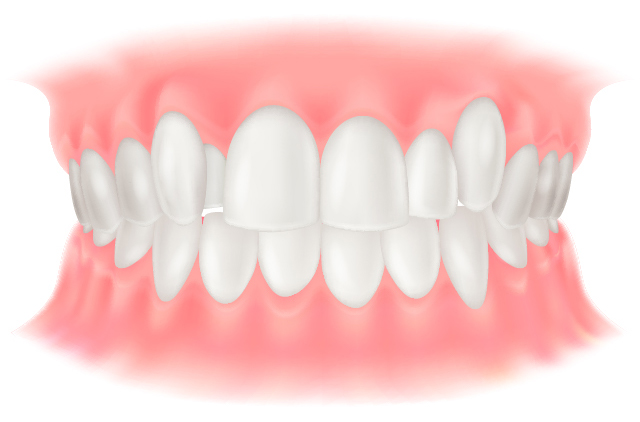

過蓋咬合

上の歯が下の歯を覆うほど深く噛んでいる状態です。下の歯が上の歯ぐきを刺激して口内炎ができたり、前歯が乾いて虫歯の原因になることがあります。